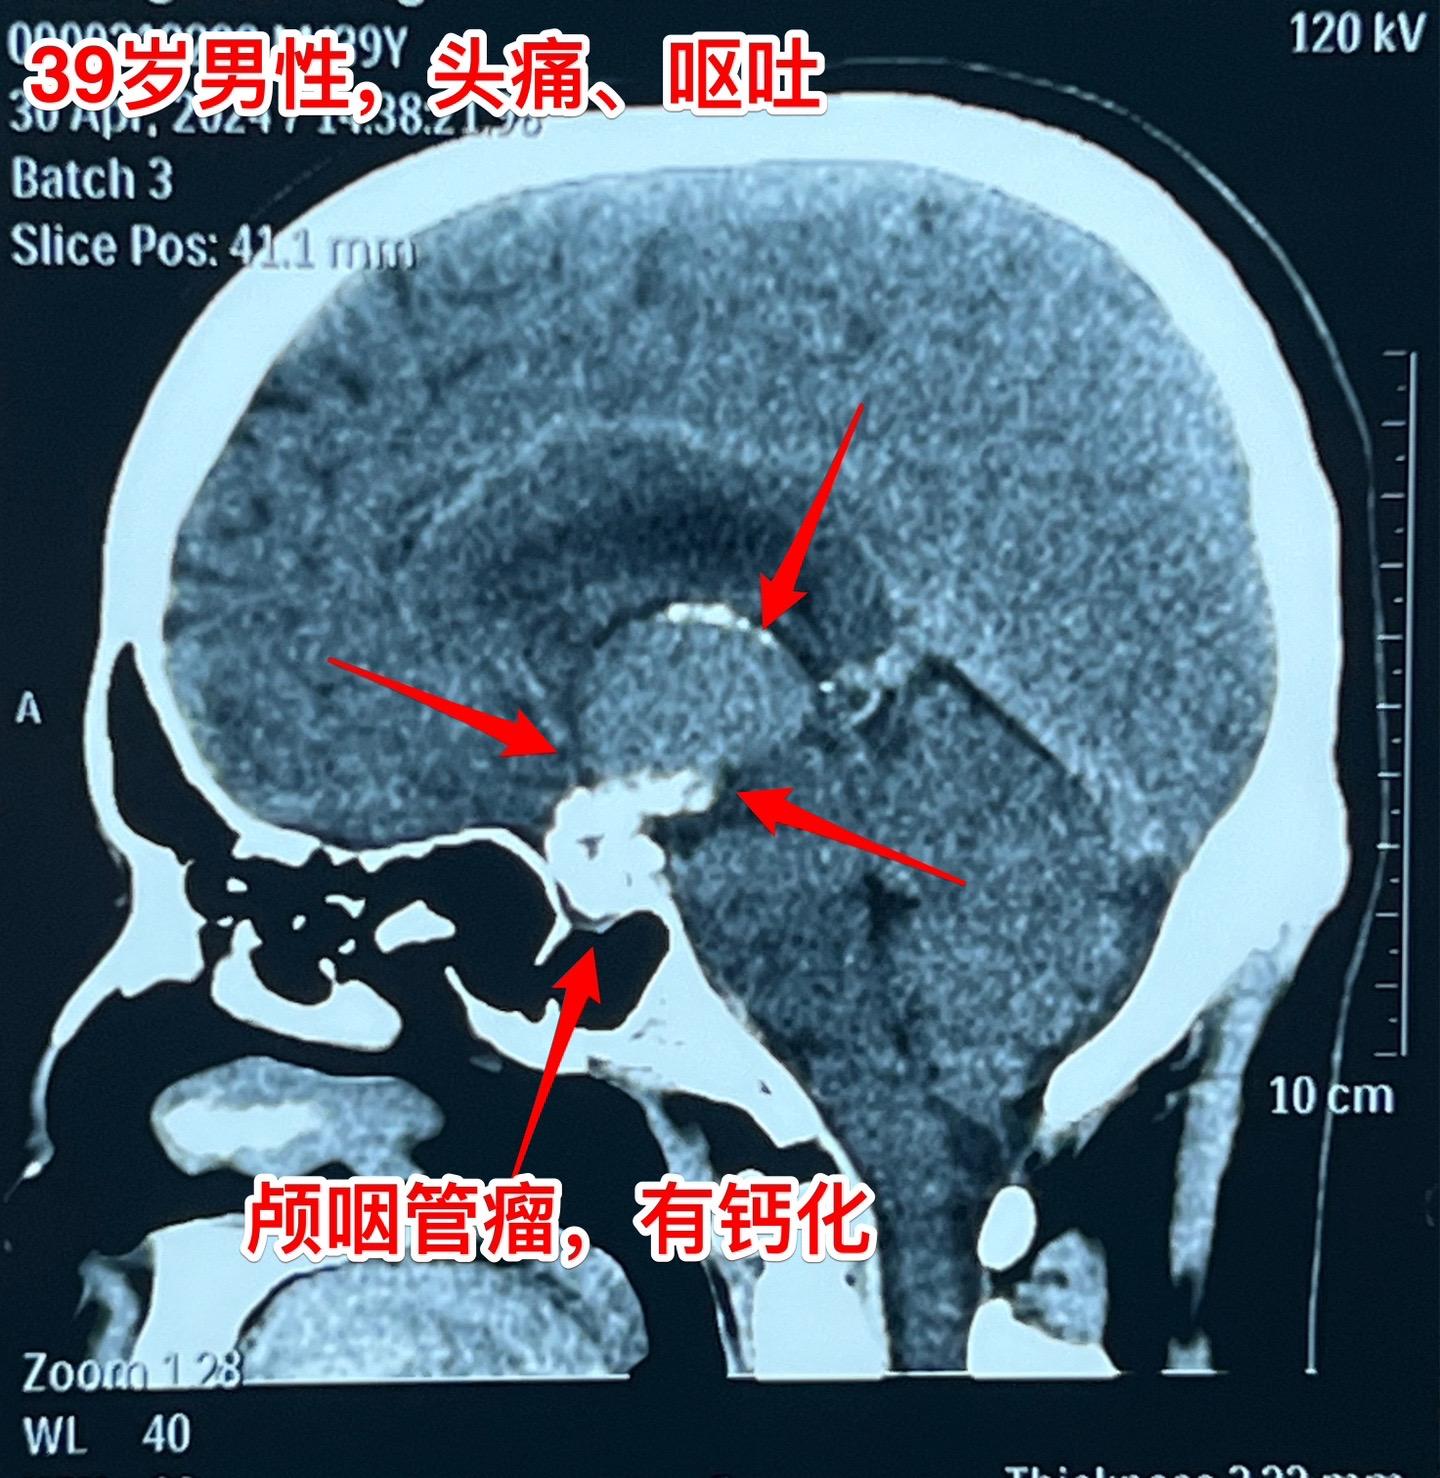

五月六日的颅咽管瘤手术。山西省男性,39岁,因为头痛、呕吐在4月29日就急匆匆的赶到三博脑科医院来住院。病因是颅咽管瘤造成颅压高,不能正常吃东西了。住院后用药物治疗,头痛症状减轻,也不呕吐,能正常进食。从图片可以看出这个颅咽管瘤属于细长型,从垂体窝延伸到第三脑室内,垂体窝里有大块钙化,手术是有难度的。

五一假期一过就排上手术,顺利切除肿瘤,手术后CT结果很让人满意,希望肿瘤不复发。